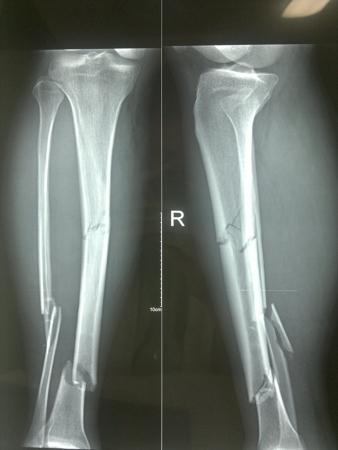

微创手术治疗胫骨干粉碎性骨折

胫腓骨粉碎性骨折并伴有腓总神经损伤,胫骨用髓内钉固定,腓骨用钢板

小腿粉碎性骨折图片

粉碎性骨折图片

粉碎性骨折x光

粉碎性骨折x光片